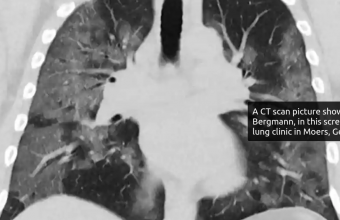

У 70% перехворілих Covid-19 за чотири місяці після інфікування виявлено порушення одного або декількох внутрішніх органів.

Учені обстежили понад 200 осіб, інфікованих Covid-19. Середній вік учасників становив 44 роки. Оцінка стану була завершена за 105-160 днів після появи їхніх симптомів.

За словами вчених, за кілька місяців після появи перших симптомів коронавірусу в учасників все ще спостерігалися кардіореспіраторні (92%) і шлунково-кишкові (73%) ураження, а у 42% людей було десять або більше уражень різних органів.

Дослідники стверджують, що були докази легкого ураження органів серця (32%), легенів (33%), нирок (12%), печінки (10%), підшлункової залози (17%) і селезінки (6%).